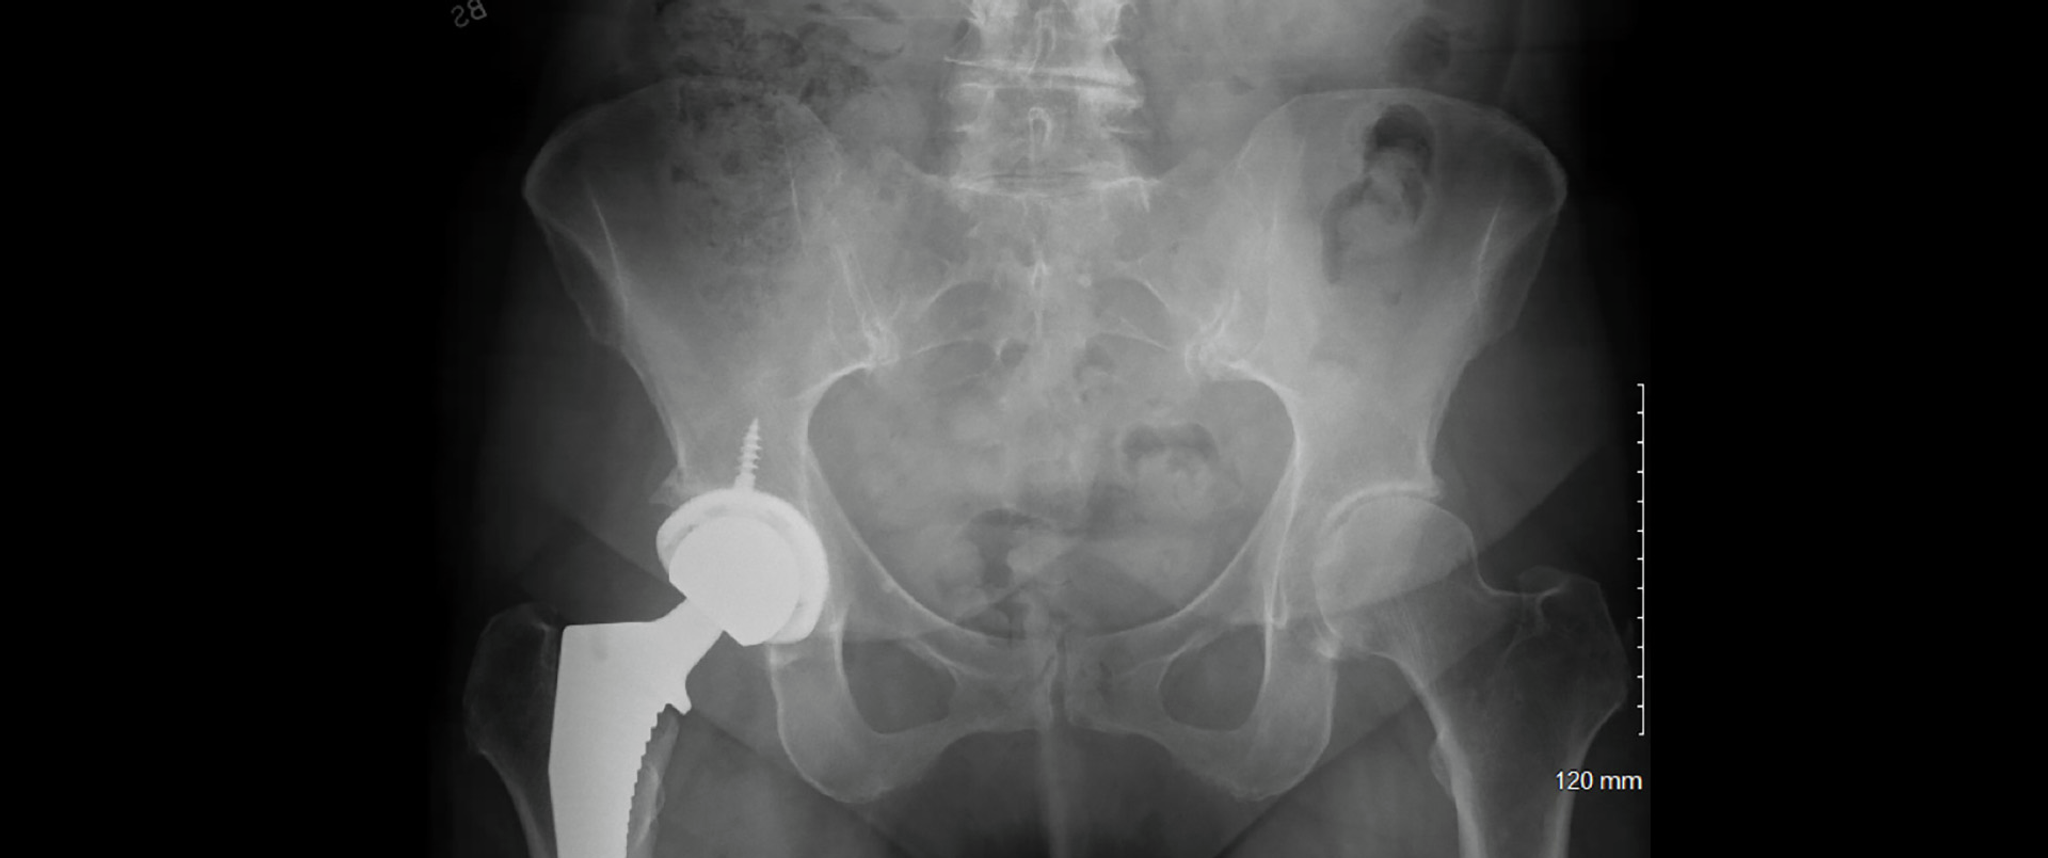

An X-ray representing the pelvic and hip bones of a patient with osteoarthritis of the hip prior to surgery.

Figure 1. Preoperative AP pelvis demonstrating severe (Tonnis grade III) hip osteoarthritis and history of inflammatory arthritis.

Mrs. M, 66-years-old, was referred to orthopaedic surgeon Matthew J. Poorman, MD, at Penn Medicine Lancaster General Health (LGH) for an evaluation of right hip pain of one year’s standing. During this time, a series of right hip imaging studies found moderate to severe degenerative changes with joint space narrowing, subchondral sclerosis/cysts and osteophyte formation, confirming progressive degenerative disease at her hip.